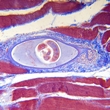

Trichinosis (or trichinellosis) is a complex disease about which little is known. It is caused by eight different species of round worm in the genus . These parasites can be found in animals on all continents but Antarctica. Artic bears harbor a species... read more